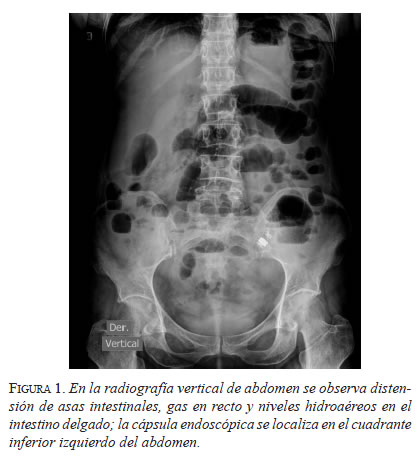

En el examen físico se encontró estabilidad hemodinámica, el abdomen estaba distendido y no doloroso, y no había signos de irritación peritoneal. En la radiografía vertical simple de abdomen se apreció distensión de asas intestinales y múltiples niveles hidroaéreos en el intestino delgado, y la cápsula endoscópica estaba localizada en el cuadrante inferior izquierdo del abdomen (figura 1).